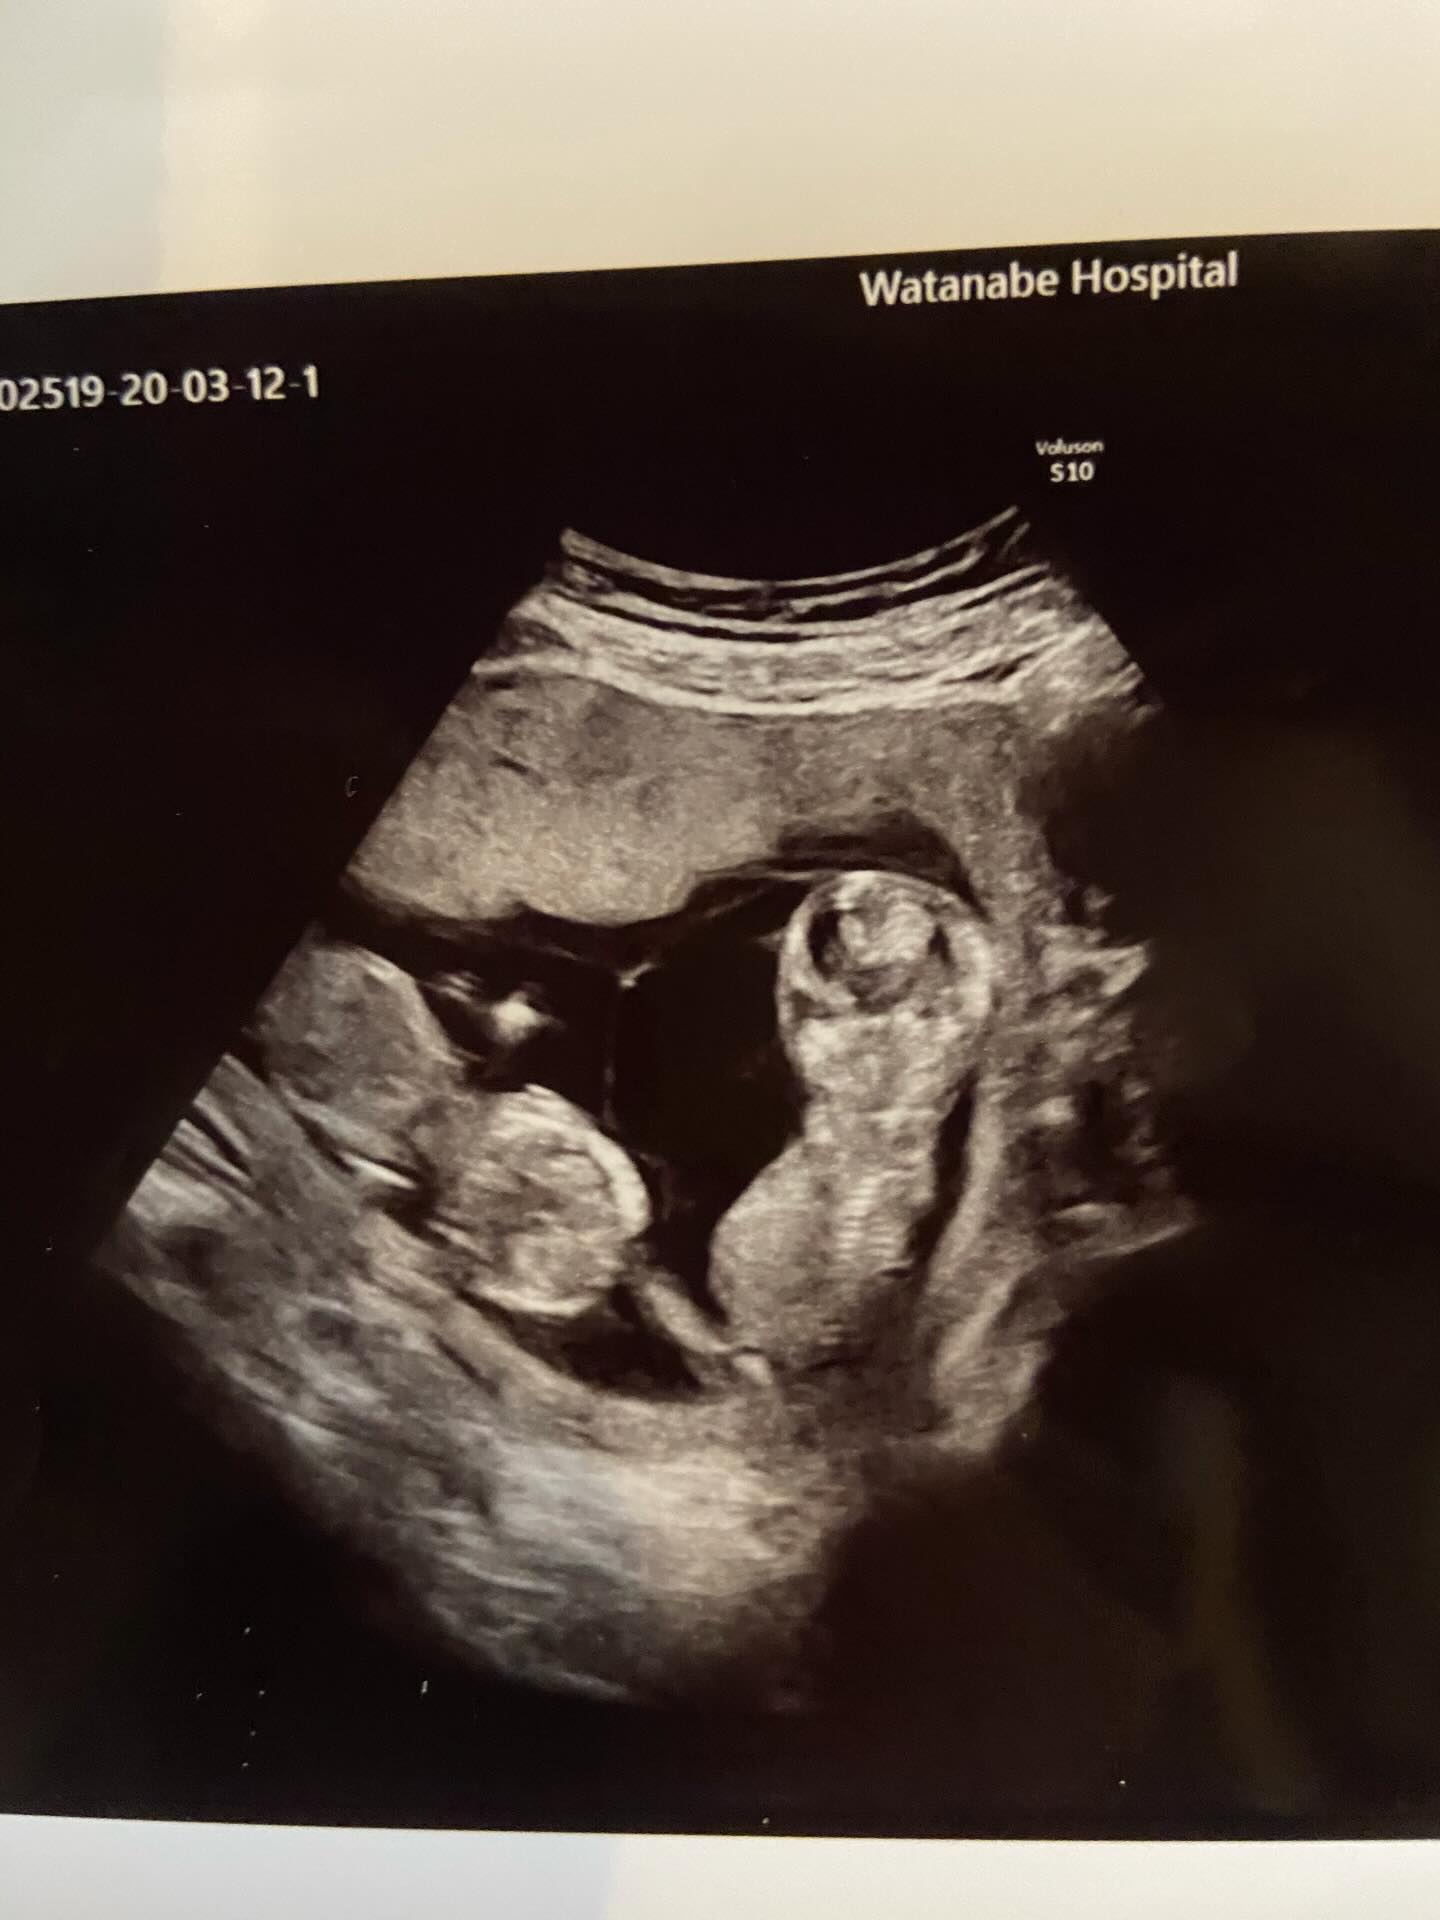

お腹の中の双子ちゃんたち

ママさんが投稿したのは、妊娠13週目のエコー写真。お腹の中で育った小さな命は、元気な双子の赤ちゃんとして誕生しました。